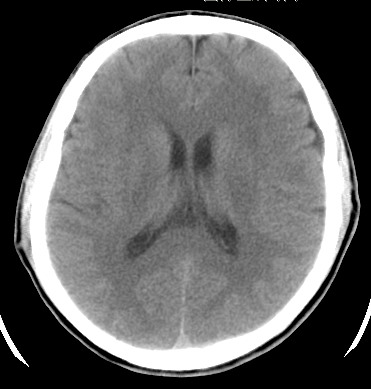

标题: CT17787:头ct,请帮忙看看右顶部有无异常 [打印本页]

标题: CT17787:头ct,请帮忙看看右顶部有无异常

男,58岁,偶有头疼

未见明显异常。右顶部低密度影为深入的脑沟。

增宽的脑沟!无异常!

是宽大的脑沟,局部不象有萎缩现象

增宽的脑沟

诊断依据:

低密度影周围脑组织边缘均有一层脑灰质覆盖。

正常啊,是对右顶增宽脑沟有疑问吗